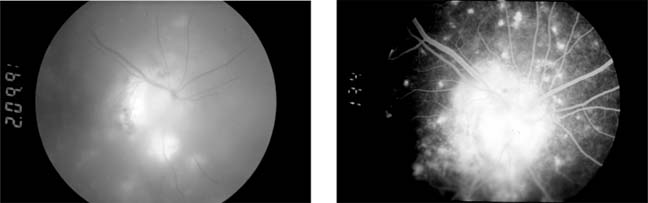

SARCOIDOSIS (new window  Figures 15-25 and new window  15-26)

Sarcoidosis is a multisystem disease with pulmonary, ocular (uveitis), cutaneous, and reticuloendothelial system manifestations. A granulomatous uveitis may be accompanied by cells in the vitreous periphlebitis, disk swelling, retinal neovascularization, and choroidal disease. New vessels may require photocoagulation. The systemic disease is controlled by the administration of oral corticosteroids and occasionally immunosuppressants. Infiltrative optic neuropathy is a rare cause of progressive severe visual loss.

Figure 15-25

Figure 15-25: Sarcoidosis. Focal periphlebitis and disk leakage may respond dramatically to systemic corticosteroids. Left: Before treatment. Right: After 6 weeks of treatment with prednisolone, 30 mg daily.

Figure 15-26

Figure 15-26: Sarcoidosis. Retinal pigment epithelial and choroidal disease may be very distinctive (left) and highlighted by fluorescein angiography (right).